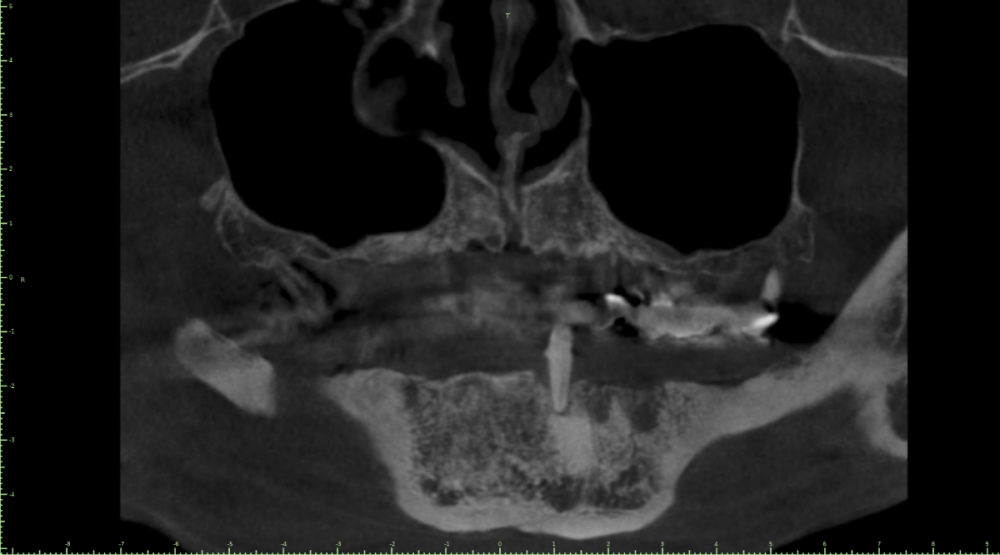

Geronima Опубликовано 29 апреля, 2022 Поделиться Опубликовано 29 апреля, 2022 Здравствуйте ! Был недавно в минской стоматологии где к сожалению мне не смогли помочь. В Финансах не ограничен. Нужны зубы, посоветуйте чтобы было качественно и надежно. Одномоментную имплантацию не рассматриваю вообще. К хорошему специалисту готов лечь в кресло хоть завтра. 3D Снимок зубов на гугл диске. https://drive.google.com/file/d/1Qx95HXPfq-zzHC1rwvTu9yMXEnugwHR-/view?usp=sharing Ссылка на комментарий